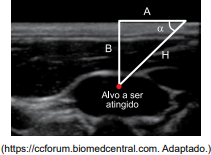

Para realizar o cálculo da diferença de altitude (altura) entre dois pontos A e